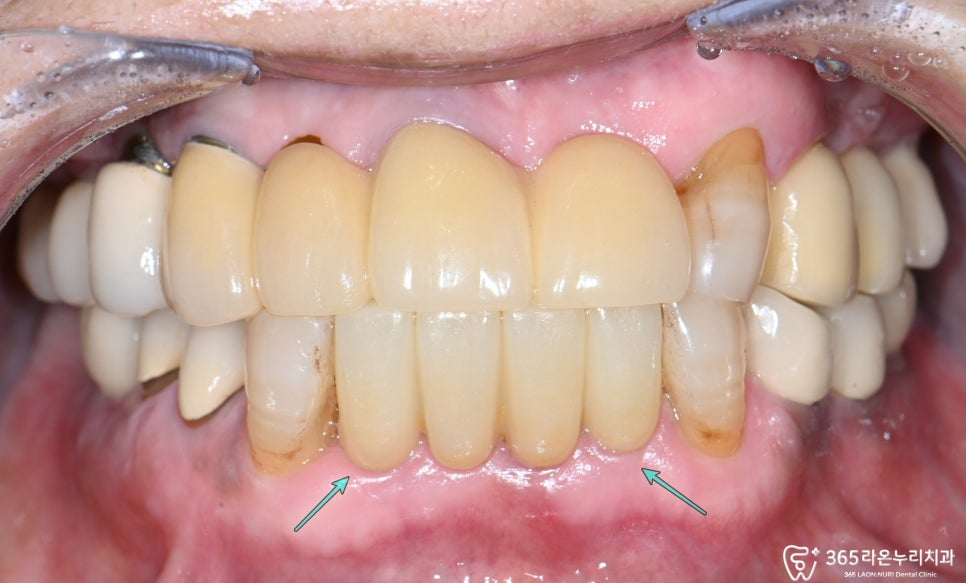

그리고 심미적으로 중요한 부위이기 떄문에

임시치아를 먼저 수복하여

최종 보철 형태 및 교합을 확인해 줍니다.

그 후 지르코니아 크라운을 제작하면서

마무리를 하게 됩니다.

2025.6.12

보철을 자연 치아와

큰 차이가 없도록

꼼꼼히 제작하여 씌워야 됩니다.

크라운은 자연치처럼

심미적인 형태로 제작되어,

앞 역할을 톡톡히

해내고 있습니다.